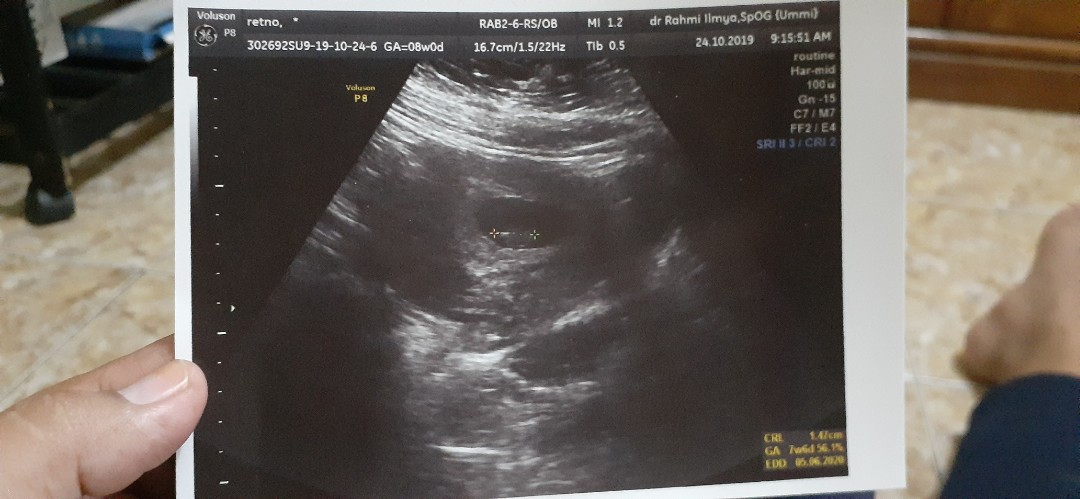

bund mau tanya ada kah tmn2 di sini yg USG 6 minggu tapi blm kelihatan janin nya apakah termasuk janin tdk berkembang ya

Tuh bund usg yang bagus untuk mengetahui

Yg 8 week aja baru 1cm